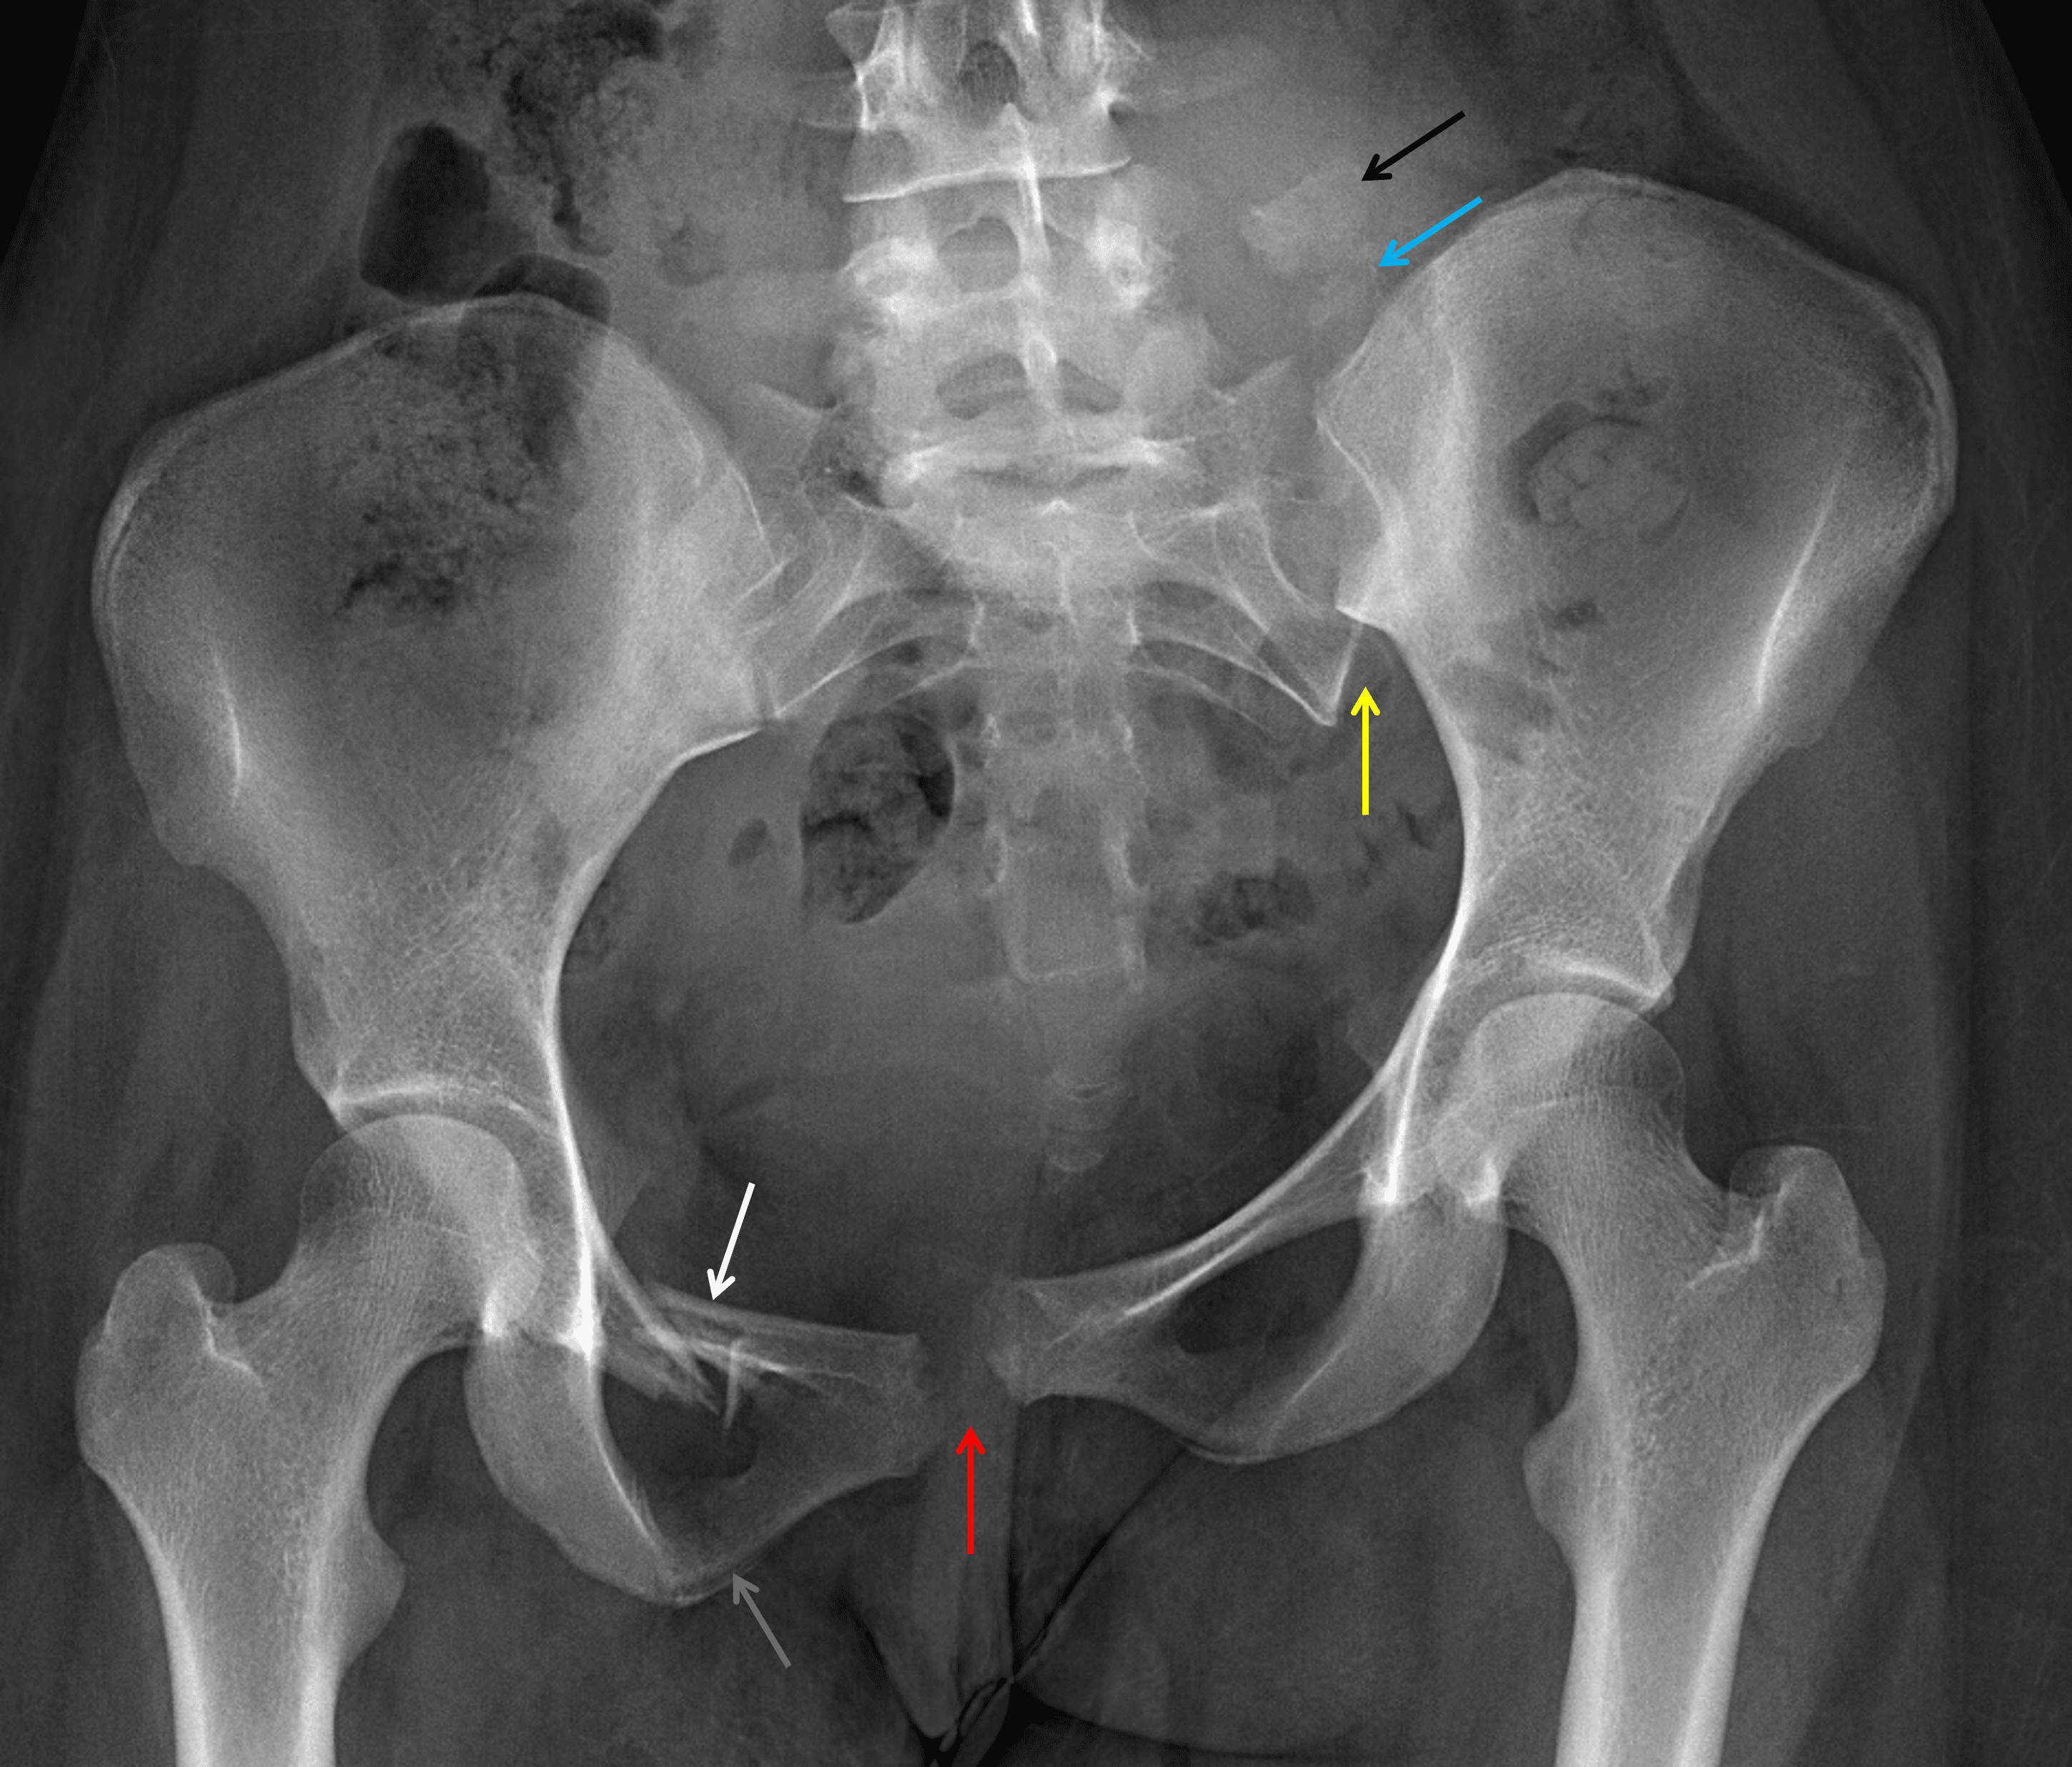

- Widening and offset of the pubic symphysis and left sacroiliac joint with superior translation of the left hemipelvis

- Acute left sacral ala fracture with a superiorly displaced S1 fragment

- Acute comminuted right superior pubic ramus fracture and nondisplaced right inferior pubic ramus fracture

- Acute laterally distracted fracture of the left L5 transverse process

Vertical shear pelvic ring injury

Acute unstable vertical shear pelvic ring injury with symphyseal and left sacroiliac joint diastasis, superior left hemipelvic translation, and fractures of the left sacral ala (with superiorly displaced S1 fragment), right superior (comminuted) and inferior pubic rami, and left L5 transverse process (laterally distracted).

Widening and offset of the pubic symphysis (red arrow) and left sacroiliac joint (yellow arrow). Fractures of the right superior (white arrow) and inferior (gray arrow) pubic rami. Displaced fractures of the left sacral ala (blue arrow) and left L5 transverse process (black arrow).